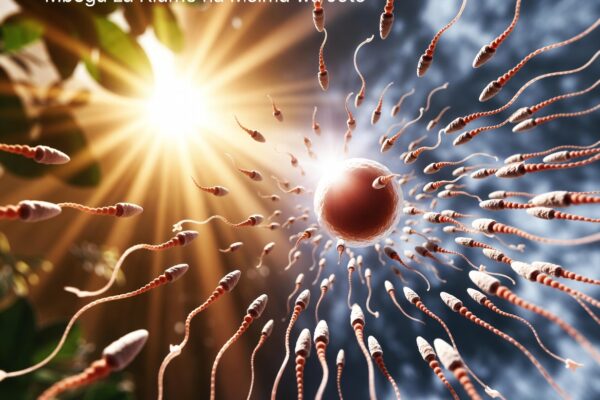

Mbegu za Kiume Zinazotungisha Mimba Zaidi Msimu wa Joto Kuliko Baridi: Utafiti Mpya wa 2026 Unaofichua Siri ya Motility na Uzazi

Mbegu za Kiume Zinazotungisha Mimba Zaidi Msimu wa Joto Kuliko wa Baridi: Utafiti Mpya Unaofichua Siri ya Msimu Mbegu za kiume (sperm) ni msingi wa uzazi wa binadamu. Lakini je, unajua kwamba uwezo wao wa kutungisha mimba unaweza kubadilika kulingana na msimu? Utafiti wa hivi karibuni unaonyesha kuwa mbegu za kiume huwa na uwezo mkubwa…